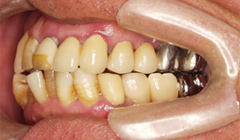

奥歯がない(65歳男性)―入れ歯で噛めない―インプラント治療後、咬合改善定期的なメインテナンスを

奥歯に入れている「入れ歯が合わない、噛めない」 患者様の症例

吉本歯科医院では、口内写真とパノラマレントゲンを撮影し、まずは顎の骨の状態まで詳しく確認しました。

写真(1)口内写真